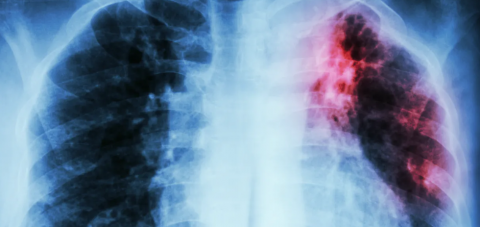

Tuberculosis y covid-19: ¿el nuevo dúo maldito?

Una preconcepción muy común en el imaginario colectivo es considerar la tuberculosis una enfermedad del siglo pasado, que ya ha sido erradicada. Cuando me preguntan sobre el tema de mi doctorado, las expresiones de estupor ante la respuesta son el denominador común al descubrir que la tuberculosis, lejos de ser un problema de salud pública minoritario, es la enfermedad infecciosa que más muertes causa al año a nivel mundial.

Las estimaciones de la Organización Mundial de la Salud (OMS) cifran en 10 millones el número de casos en 2019, entre los que se produjeron un total de 1,4 millones de decesos. Cabe puntualizar que ha sido desbancada de este primer puesto tras la abrupta aparición de, efectivamente, la COVID-19, que sumó 1,8 millones de muertes únicamente en 2020 según la OMS.

La interacción entre ambas enfermedades se encuentra bajo estricto escrutinio de la comunidad médica y científica. No solo porque comparten un [...] Leer más...